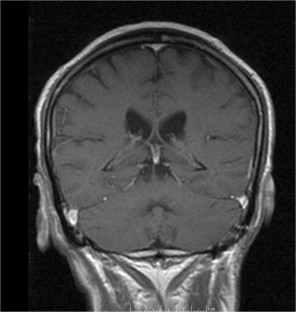

Fig. 3